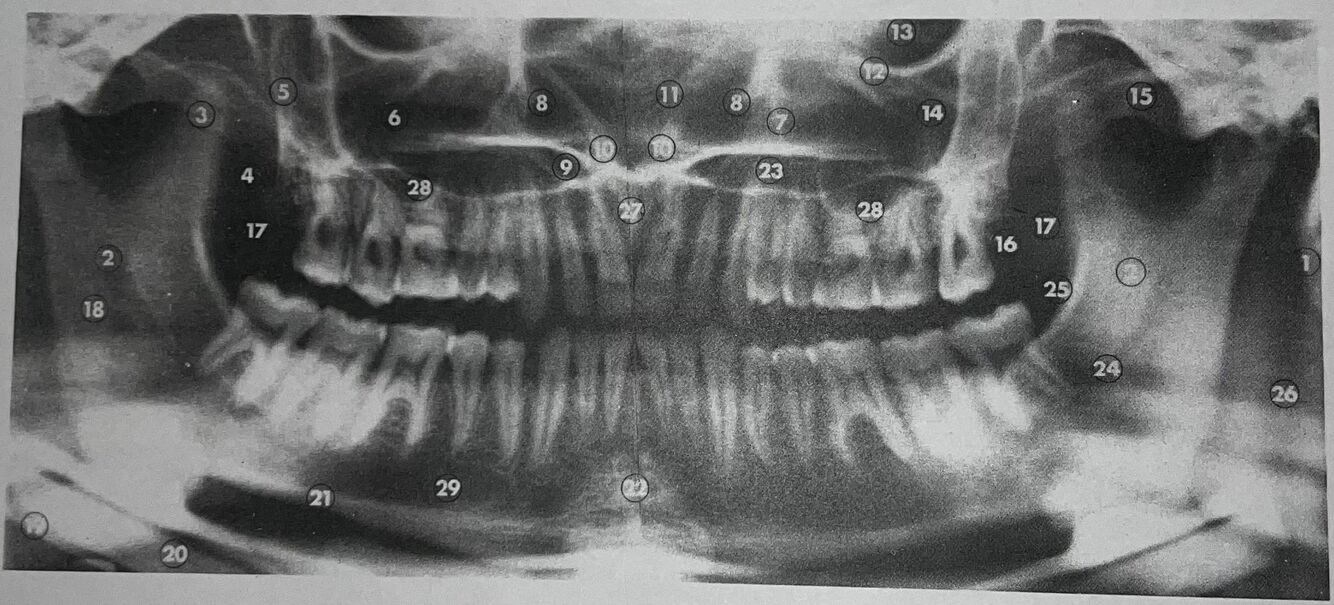

what is 1

mastoid process

what is 2

lingula

what is 3

coronoid process

what is 4

lateral pterygoid plate

what is 5

posterior wall of antrum

what is 6

antrum (maxillary sinus)

what is 7

anteromedial wall of antrum

what is 8

inferior concha

what is 9

floor of nasal fossa

what is 10

anterior nasal spine

what is 11

nasal septum

what is 12

infraorbital ridge

what is 13

orbital cavity

what is 14

malar process

what is 15

zygomatic arch

what is 16

maxillary tuberosity

inferior border of mandible

mental protuberance

mandibular canal

internal oblique line

superimposition of right jaw

incisive canals

floor of antrum

mental foramen